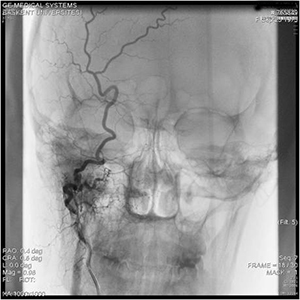

37 yaşında bayan hasta sağ kulak arkasında ağrı ve uğultu şiakyeti ile başvurdu. Yapılan incelemlerde kulağın sağ arka kısmında ciddi besleyici damarları olan bir kitle tespit edildi. Beyin MR incelemesinde sağda büyük Glomus jugulare tümörü görüldü ve Gamma knife tedavisi uygulandı. Hastanın tüm şiakyetlkeri geçti ve 4 yıllık takip içinde tümöründe ciddi küçülme oldu.

63 yaşında bayan hasta baş ağrısı, sol kulakta çınlama ve nabız atışını duyma şiakyetleri ile başvurdu. Sol tarafta Glomus jugulare tümörü tespit edildi. Gamma knife tedavisi sonrası hastanın tüm şikayetleri düzeldi. Kontrol Mr incelemerinde tümörün küçüldüğü izlendi.